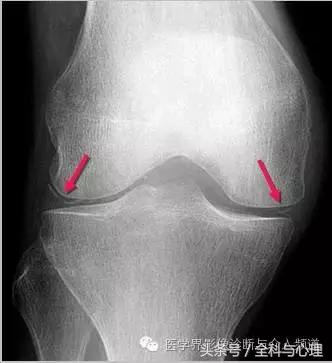

四、软骨来源的钙化:

常见于膝盖、耻骨联合、臀部、尺骨三角纤维软骨复合体、肩关节。

半月板钙化